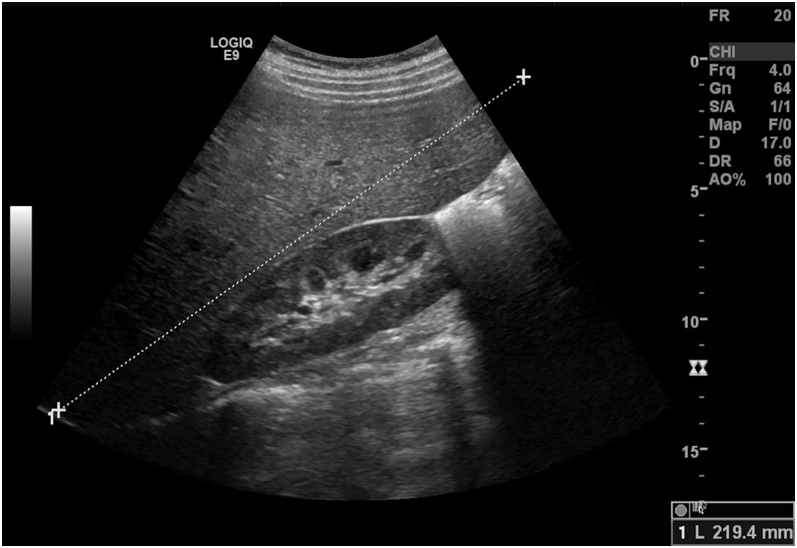

摘要:毛里亚克综合征是1型糖尿病患者中一种罕见的并发症。表现为血糖控制不佳,肝脏因肝糖原广泛沉积而肿大。行为因素还是遗传因素在其病理生理中起关键作用仍然是一个有争议的话题。我们报告一名19岁女性,患有控制不良的1型糖尿病和持续升高的肝酶,她因糖尿病酮症酸中毒和肝肿大而到达急诊室。血液检查显示没有相关的病毒性或自身免疫性肝病。短暂肝弹性图显示中度脂肪变性。肝活检结果与糖原性肝病一致。与糖原储存病相关的基因测序未发现致病变异,支持Mauriac综合征的非遗传机制。对胰岛素治疗方案和饮食计划进行综述。区分糖原性肝病与代谢功能障碍相关的脂肪性肝病通常是困难的,通常只能通过肝活检来实现。Mauriac综合征的准确诊断具有重要的预后信息,因为相关的肝肿大倾向于通过优化血糖控制而消退。学习要点:Mauriac综合征是控制不良的1型糖尿病的一种罕见并发症,表现为肝酶升高和肝糖原广泛沉积引起的肝肿大。肝活检在区分糖原性肝病和代谢相关脂肪变性肝病方面起着关键作用。适当的血糖控制常常导致毛里亚克综合征的肝肿大消退和肝酶水平正常化。

Summary: Mauriac syndrome is a rare complication in patients with type 1 diabetes. It presents with poor glycemic control and hepatomegaly due to extensive liver glycogen deposition. Whether behavioral or genetic factors play key roles in its pathophysiology remains a subject of debate. We present the case of a 19-year-old woman with poorly controlled type 1 diabetes mellitus and persistently elevated liver enzymes who arrived at the emergency department with diabetic ketoacidosis and hepatomegaly. Blood tests revealed the absence of an associated viral or autoimmune liver disease. Transient liver elastography showed moderate steatosis. Liver biopsy results were consistent with glycogen hepatopathy. Sequencing of genes associated with glycogen storage diseases revealed no pathogenic variants, supporting a non-genetic mechanism for Mauriac syndrome. Insulin regimen and dietary plan were reviewed. Distinction of glycogenic hepatopathy from metabolic dysfunction-associated fatty liver disease is often difficult and frequently only possible through liver biopsy. An accurate diagnosis of Mauriac syndrome carries important prognostic information, as associated hepatomegaly tends to regress through optimization of glycemic control.